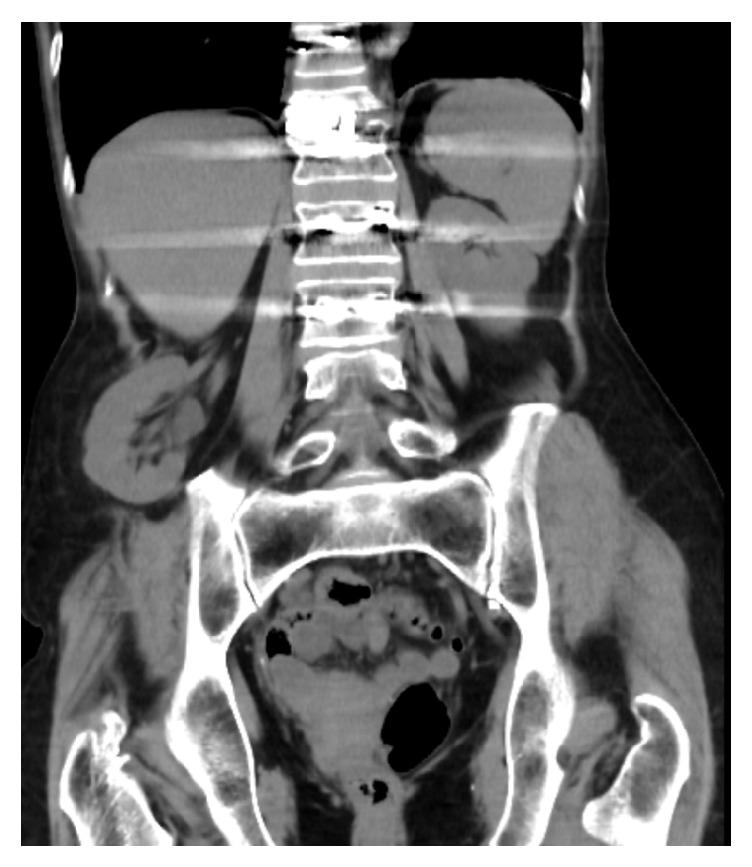

The iliac crest is a popular source for autogenous bone harvesting, but the process is rife with complications. This case report presents a patient that experienced incisional lumbar herniation of her kidney following an iliac crest bone harvesting procedure. A discussion is included on the underappreciated complications of this procedure and recommendations for improving outcomes with more thorough evaluation and documentation.

髂嵴是自体骨采集的常用来源,但该过程并发症频发。本病例报告介绍了一名患者,其在髂嵴骨采集术后出现了切口处肾腰疝。文中讨论了该手术未得到充分认识的并发症,并提出了通过更全面的评估和记录来改善手术效果的建议。